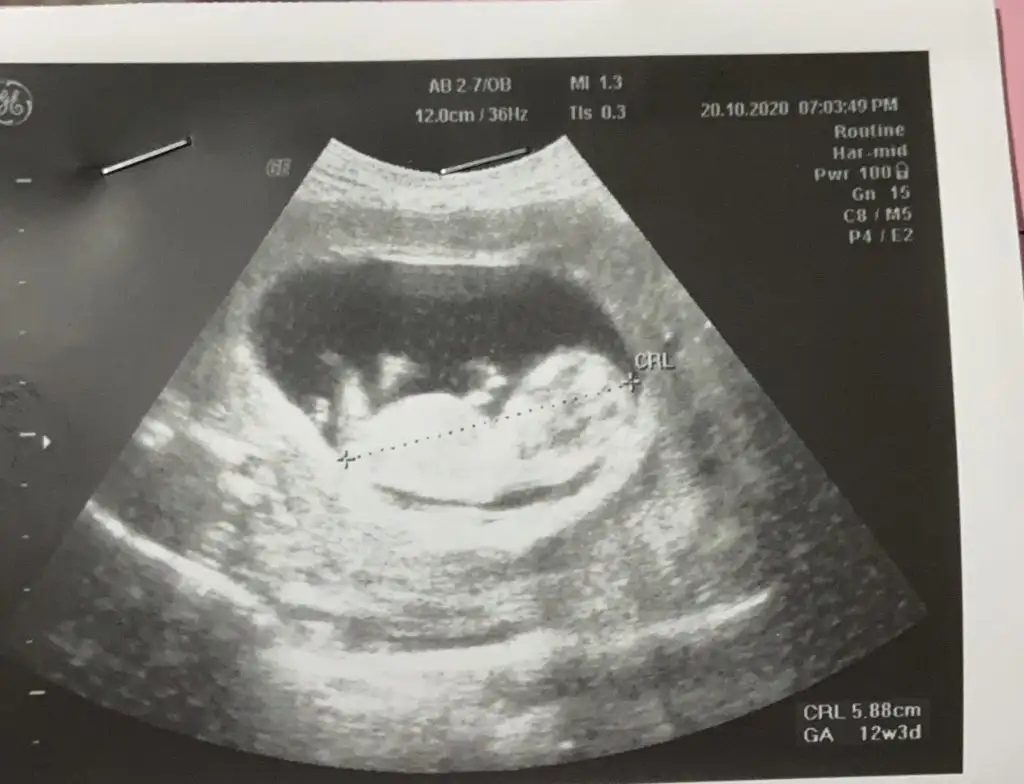

12+4..tahmininizi bekliyorum..

Eklentiler

• 20201022_181417.webp

32,1 KB · Görüntüleme: 95